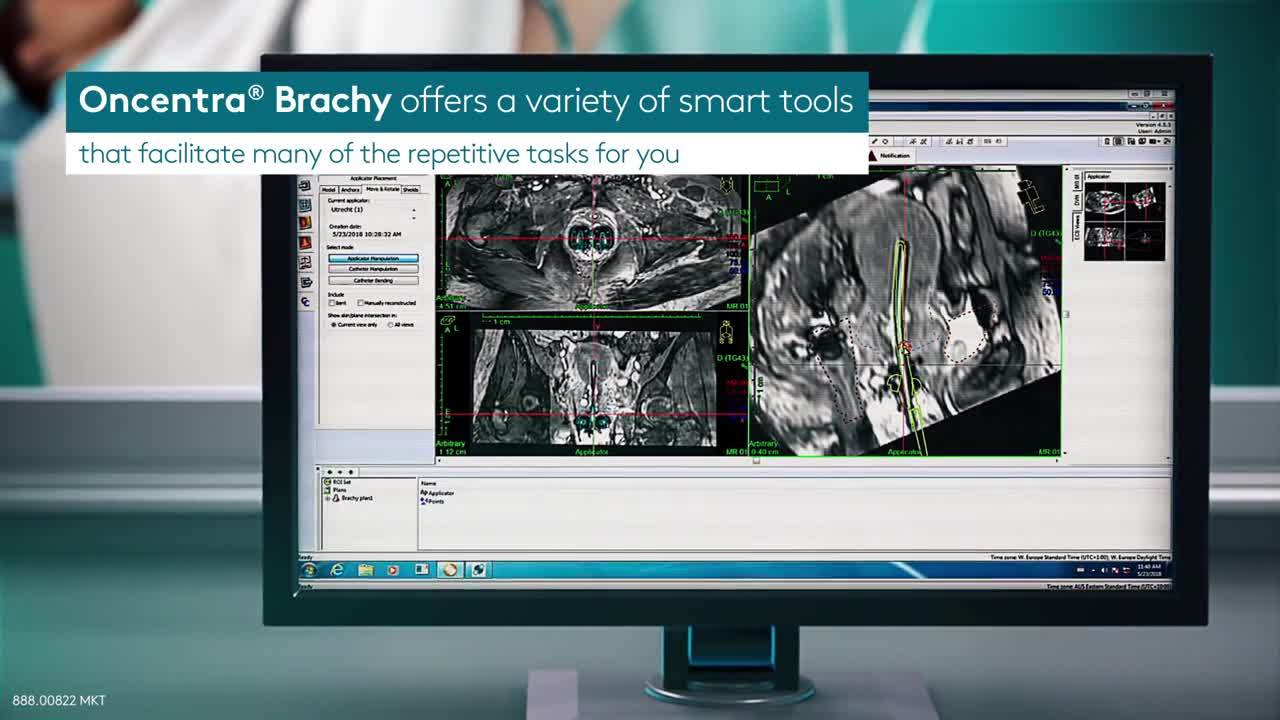

优化剂量分布的设计工作非常耗时。最新版Oncentra Brachy提供了一系列实用工具,可帮助简化许多重复性任务,例如勾画和重建。Oncentra Brachy让您能够节省时间,集中精力来确定最佳的剂量分布。

Oncentra Brachy还有助于提高乳腺癌治疗计划的准确性,让您能够轻松导航至任意层面,获取每个感兴趣区域的最相关信息。